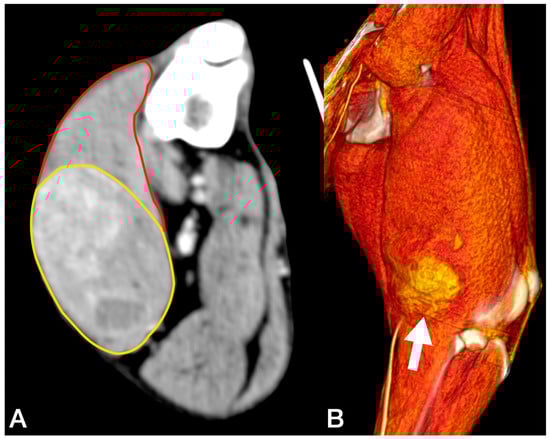

An 11.5-year-old, 28 kg, castrated male Labrador retriever was referred for a 4 cm painless, firm mass in the caudal region of the thigh. The mass had been present for several months but had recently grown. The dog showed no lameness or discomfort. Physical examination and the laboratory profile (complete blood count—CBC, biochemical values and urinalysis) were unremarkable. An incisional punch biopsy was performed during the total body CT exam (Figure 1). The histology was compatible with a soft tissue sarcoma showing chondromyxoid differentiation.

Figure 1.

Tomographic appearance of the neoplasm within the semitendinous muscle. The yellow line delimitates the mass, and the red line is the semitendineous muscle. Orientation: cranial is on the top of the figure.

Cytology of the lesion via fine needle aspiration (FNA) was not diagnostic; therefore, an incisional biopsy was performed at the time of the total body CT. This revealed a 5.8 cm × 5.5 cm, poorly defined mass confined within the biceps femoris muscle, with heterogeneous enhancement after the administration of an intravenous contrast medium (Figure 2). No lesions suggestive of metastatic spread were observed. The histology from the bioptic sample was morphologically suggestive of PWT.

Figure 2.

Tomographic appearance of the sarcoma within the biceps femoris muscle, axial view (A). The yellow line delimitates the tumours, the red line the biceps muscle 3D reconstruction, and the white arrow indicates the tumour (B).